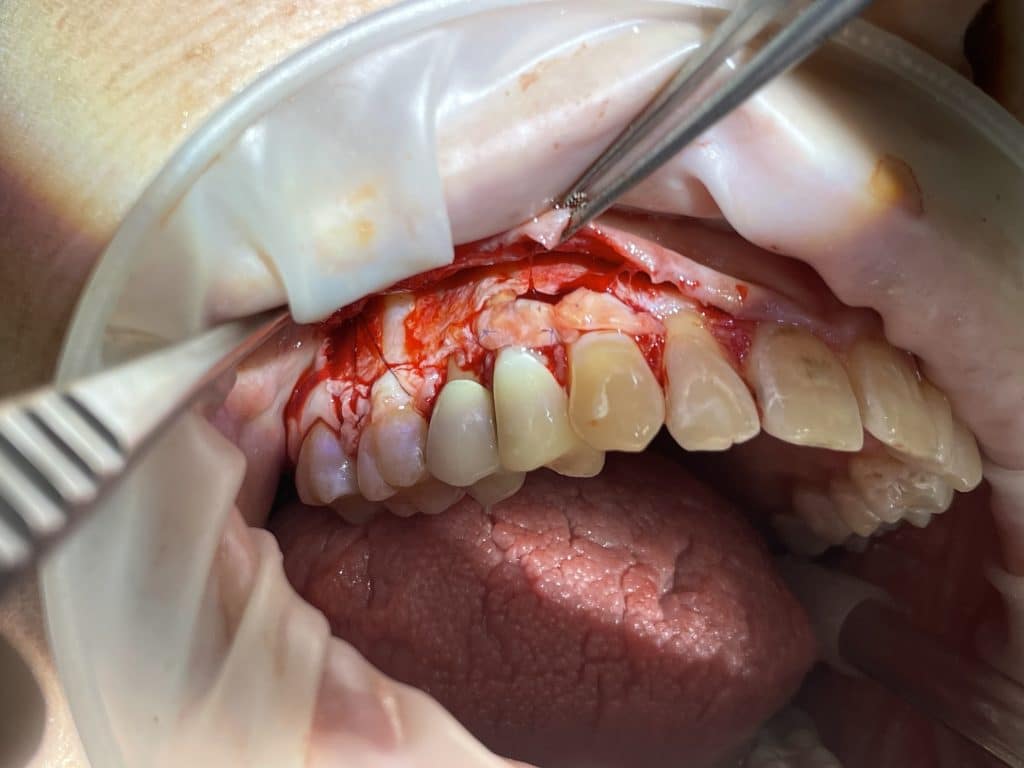

In quadrant 1, we initially removed caries and prepared tooth 14 for subsequent provisional cementation. We then performed a mucogingival surgery procedure, still utilizing the bilaminar technique with an envelope flap. The graft was harvested from the tuberosity area. The connective tissue was sutured to the periosteum, which had been left in place as the recipient bed. The primary flap was advanced coronally, covering the graft, and sutured with sling sutures in the most coronal position. In this case as well, the sutures were removed after 10 days.

paramarginal incision

checking the passivity of the covering flap

full and split thickness flap